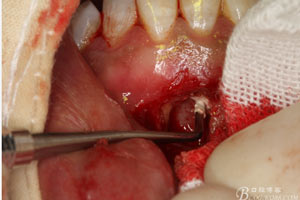

圖10.從唇側(cè)側(cè)穿除切除31根尖部分。

圖11.根尖切除后,并搔刮干凈后的31缺損的骨腔情況